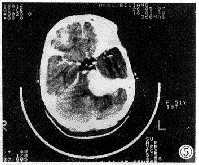

听神经瘤 桥小脑角区最常见肿瘤。本组中占80%(12/15),与文献报道基本相符。肿瘤源于前庭神经鞘膜管内部分,生长慢,常见于成人。CT表现有如下特点:①平扫多为低或低等混杂密度灶,低密度为主(7/12),边缘不清。②增强后都有明显强化,多为不均匀性强化(8/12),囊变坏死区不强化,也可呈花环状强化;强化灶边缘清楚而不规则。③骨窗见内听道口扩大(12/12),典型改变呈喇叭口状;病变以内听道口为中心;多数病例病变以窄基与岩骨相连(9/12)。④其它表现:部分病例见与肿瘤相邻桥小脑角池扩大,国外学者认为它代表肿瘤压迫脑组织,致该部分脑组织萎缩,此征象可除外脑内肿瘤(图1、2、3)。

图1、2、3 右桥小脑角听神经瘤。平扫呈低密度、强化明显、内有囊变坏死区、内听道“喇叭口”改变。